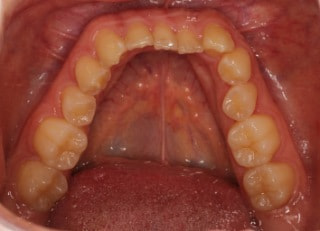

治療後(2年11ヶ月後)